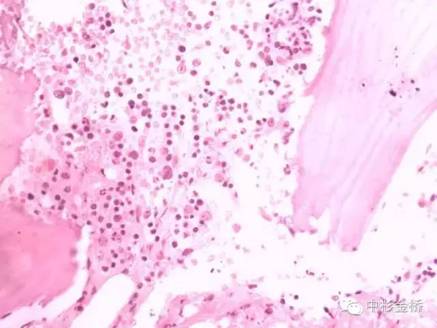

Rapidcal.Immuno脫鈣處理的骨髓標(biāo)本,易于2?m連續(xù)完整切片,鏡下結(jié)構(gòu)清晰,細(xì)胞核與漿顏色鮮艷;常規(guī)硝酸脫鈣的骨髓標(biāo)本,鏡下細(xì)胞核與漿顏色對比不明顯,染色質(zhì)不清晰。免疫組化實(shí)驗(yàn)中,Rapidcal.Immuno脫鈣處理的骨髓標(biāo)本,CD3、CD4、CD79a、CD20所標(biāo)記的T細(xì)胞和B細(xì)胞定位準(zhǔn)確,陽性表達(dá)強(qiáng),背景清晰。常規(guī)硝酸脫鈣的骨髓標(biāo)本,抗原部分丟失,標(biāo)記物陽性結(jié)果表達(dá)較弱,背景有部分非特異性著色。

HE差

HE好